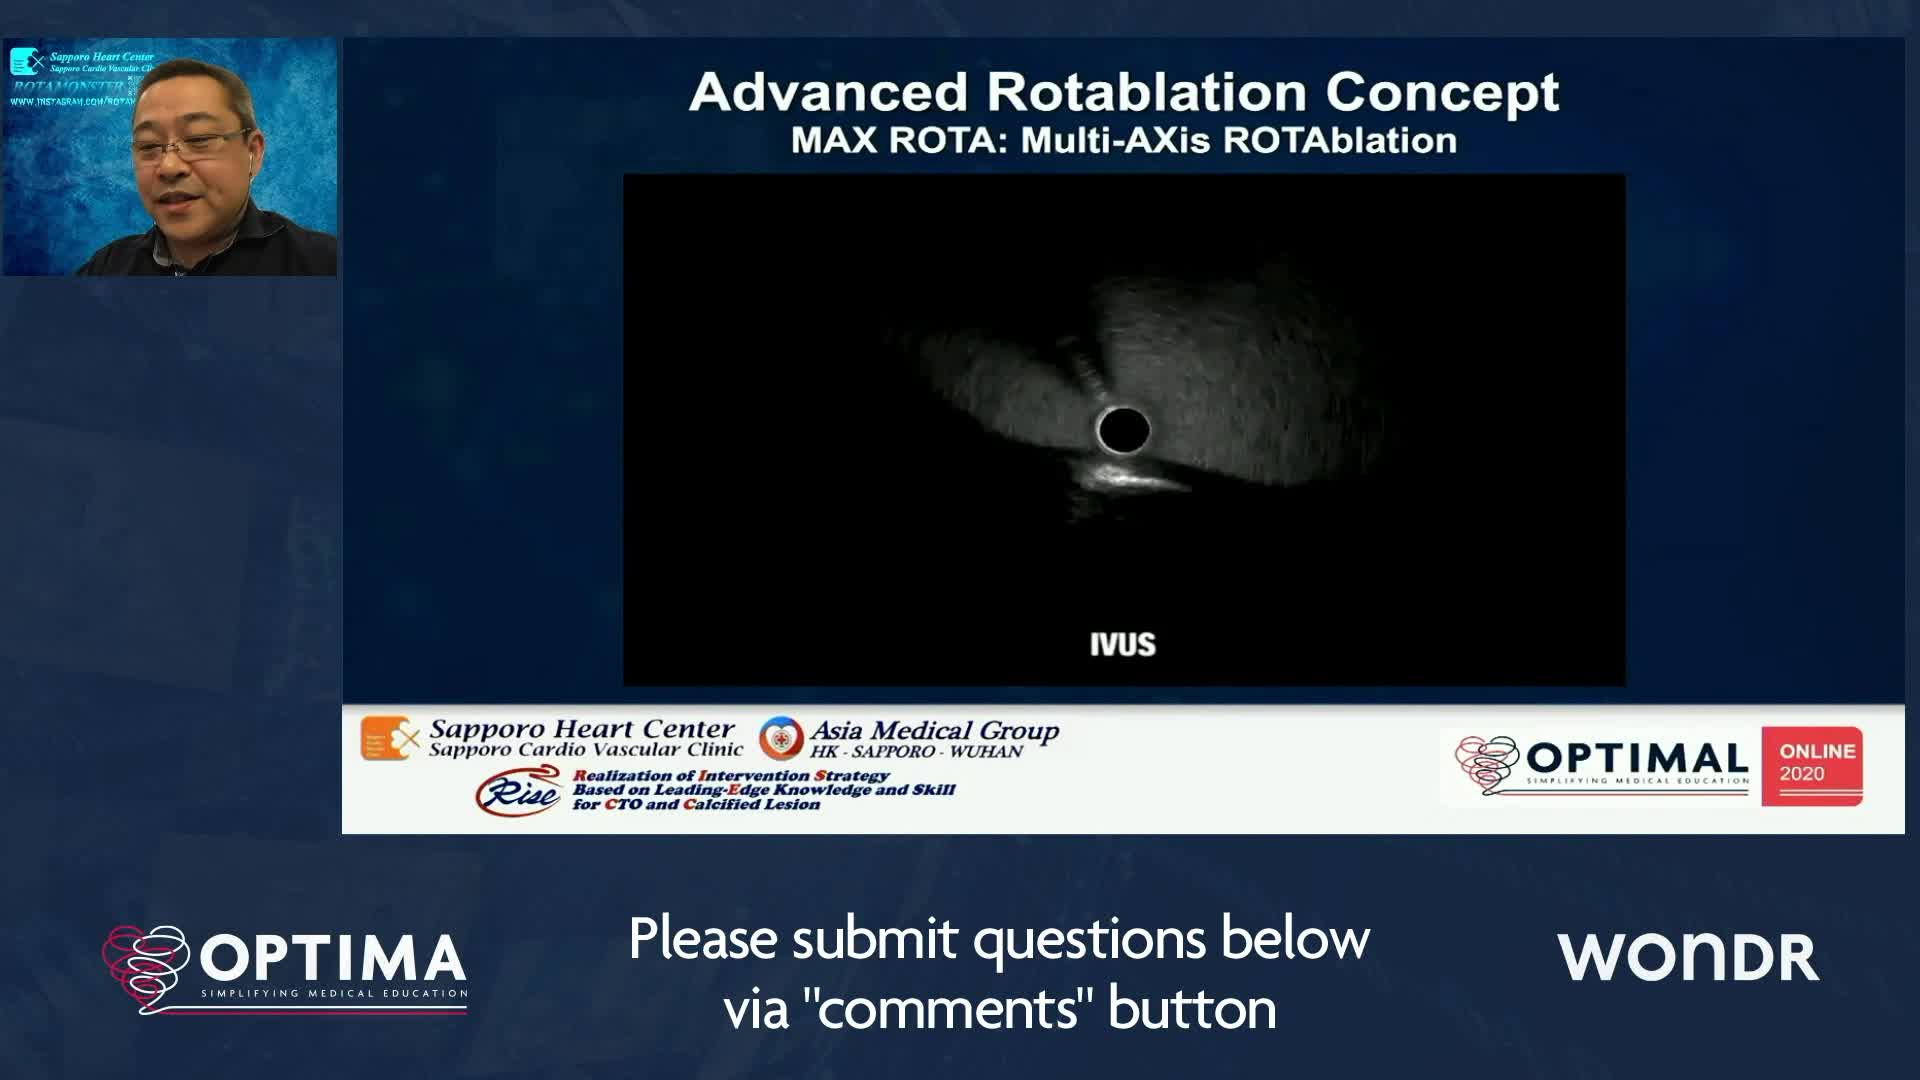

Treatment of coronary arterial calcium (CAC) has being redefined. We explore the interaction between CAC and patient...